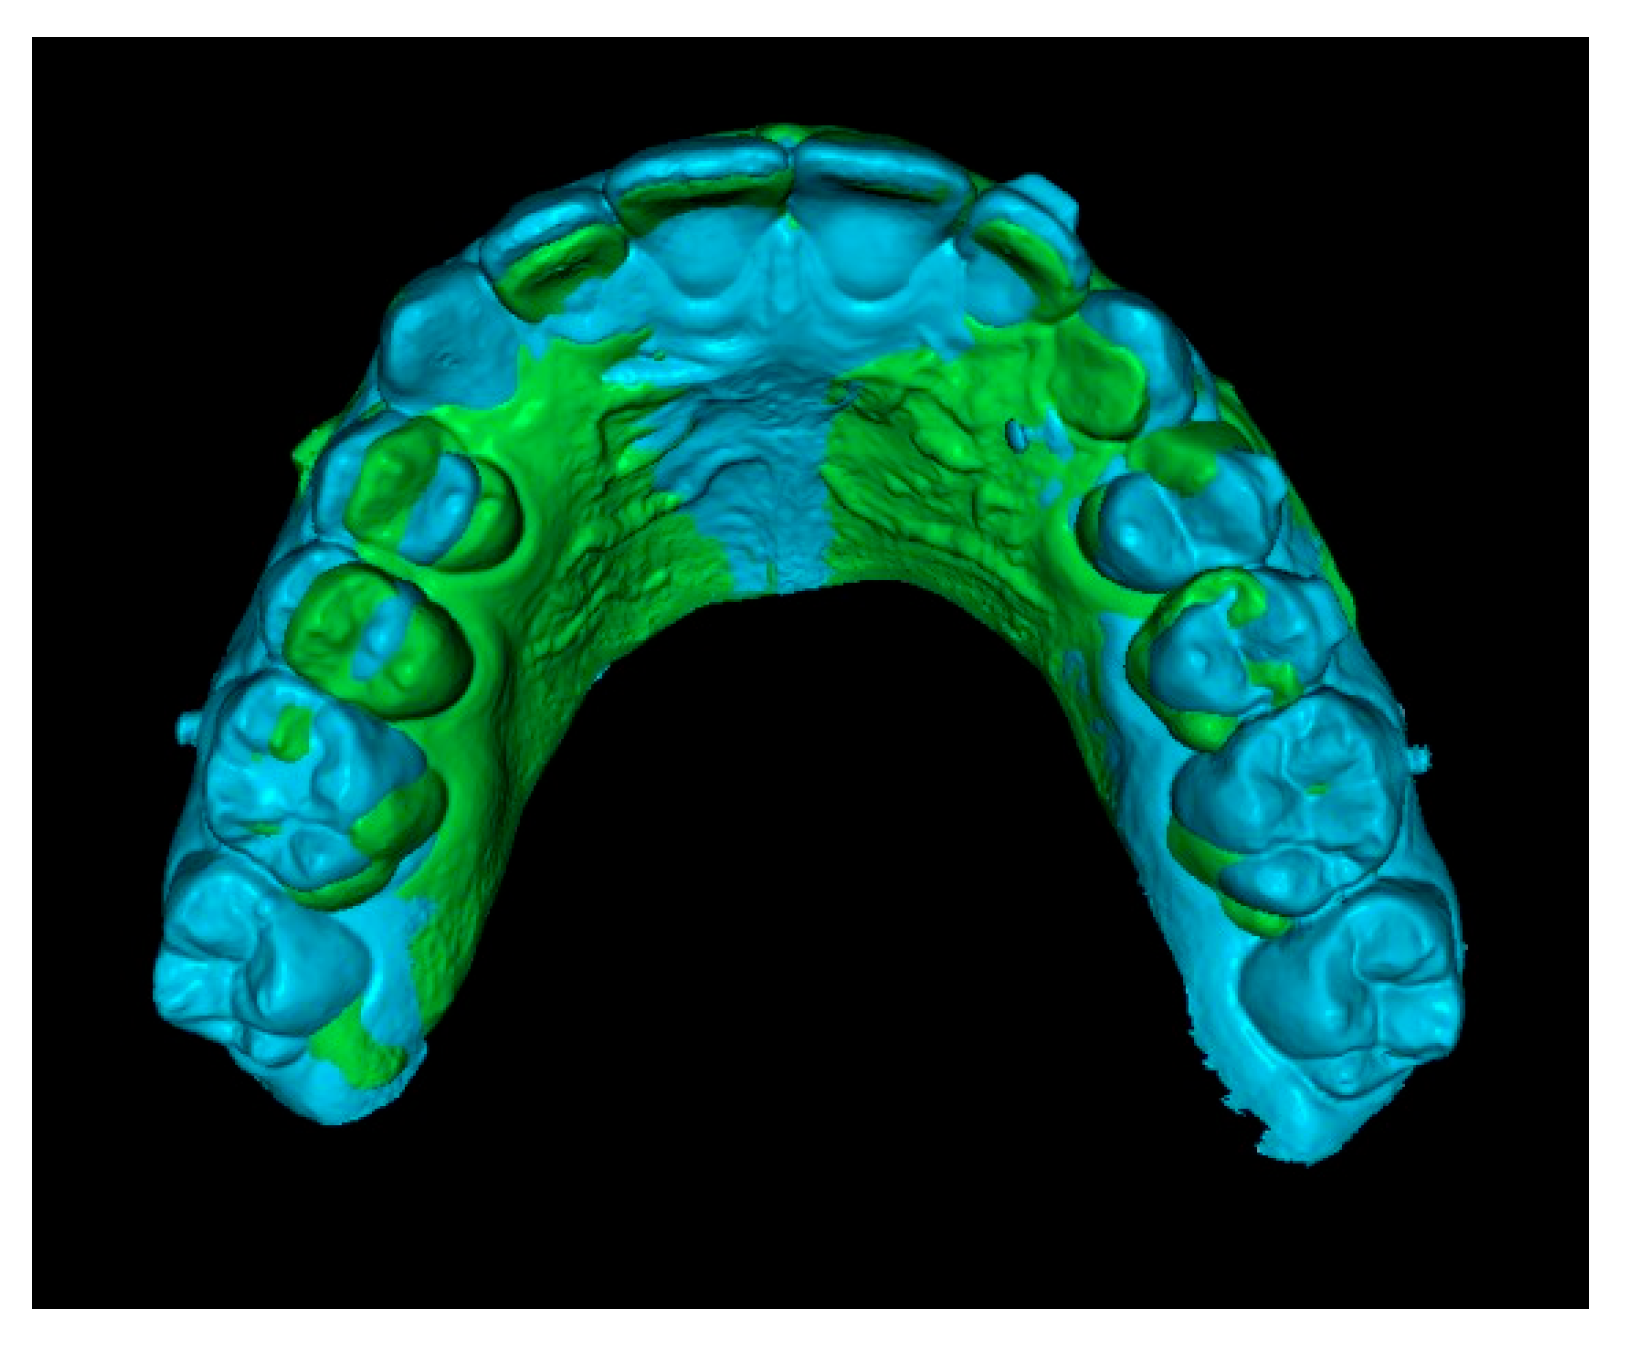

Second step: Superimposition of Initial CBCT and Initial STL Scans.

In this step, the segmented teeth from the initial CBCT scan were superimposed onto the initial STL file. This was achieved by marking corresponding points on several teeth throughout the dental arch, ensuring accurate alignment (Figure 4). Despite the morphological differences between the CBCT and STL models, particularly related to the canine region, as the permanent canine was still impacted and therefore visible only in the CBCT, corresponding anatomical landmarks were carefully selected on both models to enable accurate superimposition and comparison. The deciduous canine is only visible in the intraoral scanner data, as it was not segmented and included in this figure despite being present in the CBCT (Figure 4).

Figure 4.

Superimposition of segmented teeth from initial CBCT and initial STL.

Since orthodontic traction had not yet started, the position of the teeth remained unchanged between scans, allowing precise registration. As a result, the initial STL was effectively combined with the three-dimensional position of the IC derived from the CBCT (Figure 5).

Figure 5.

Initial STL with the IC from the CBCT scan.